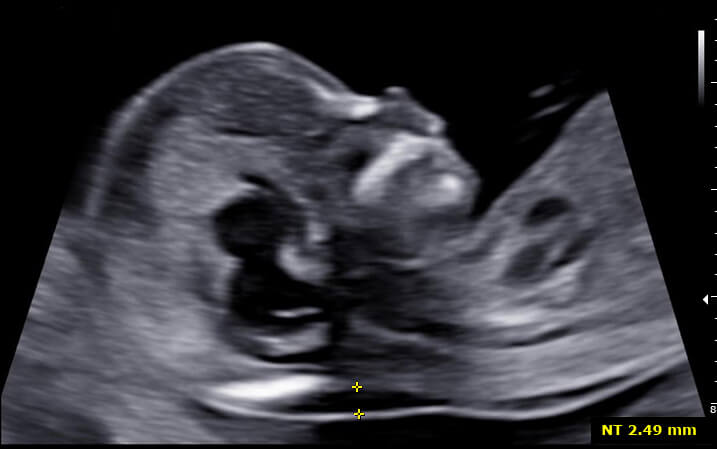

Translucência nucal

A translucência nucal corresponde ao espaço livre na parte posterior do pescoço fetal, entre a coluna e a borda da pele, sendo medida no plano sagital médio fetal e podendo representar maior risco de alterações genéticas fetais quando aumentada.

Realiza-se a triagem com ultrassom morfológico entre 11 semanas e 0 dias e 13 semanas e 6 dias. Entre os achados do exame que associam-se a aneuploidias estão:

- Translucência nucal (TN) maior ou igual a 3 ou 3,5 mm;